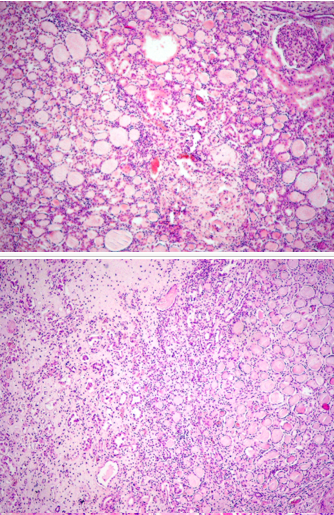

Identify

Renal cell carcinoma (clear cell carcinoma) (369)